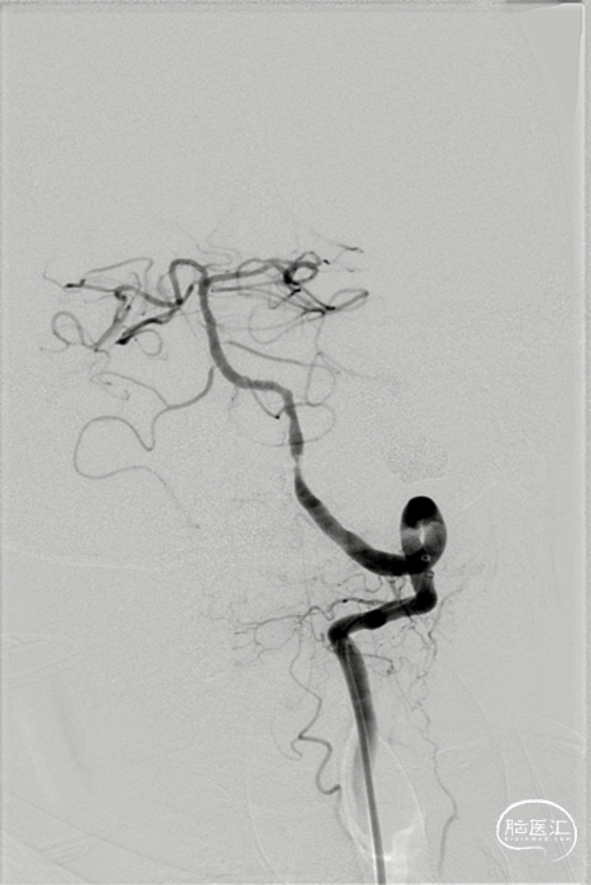

4.5mm*20mm自膨支架释放

复查造影

术前造影

术后造影